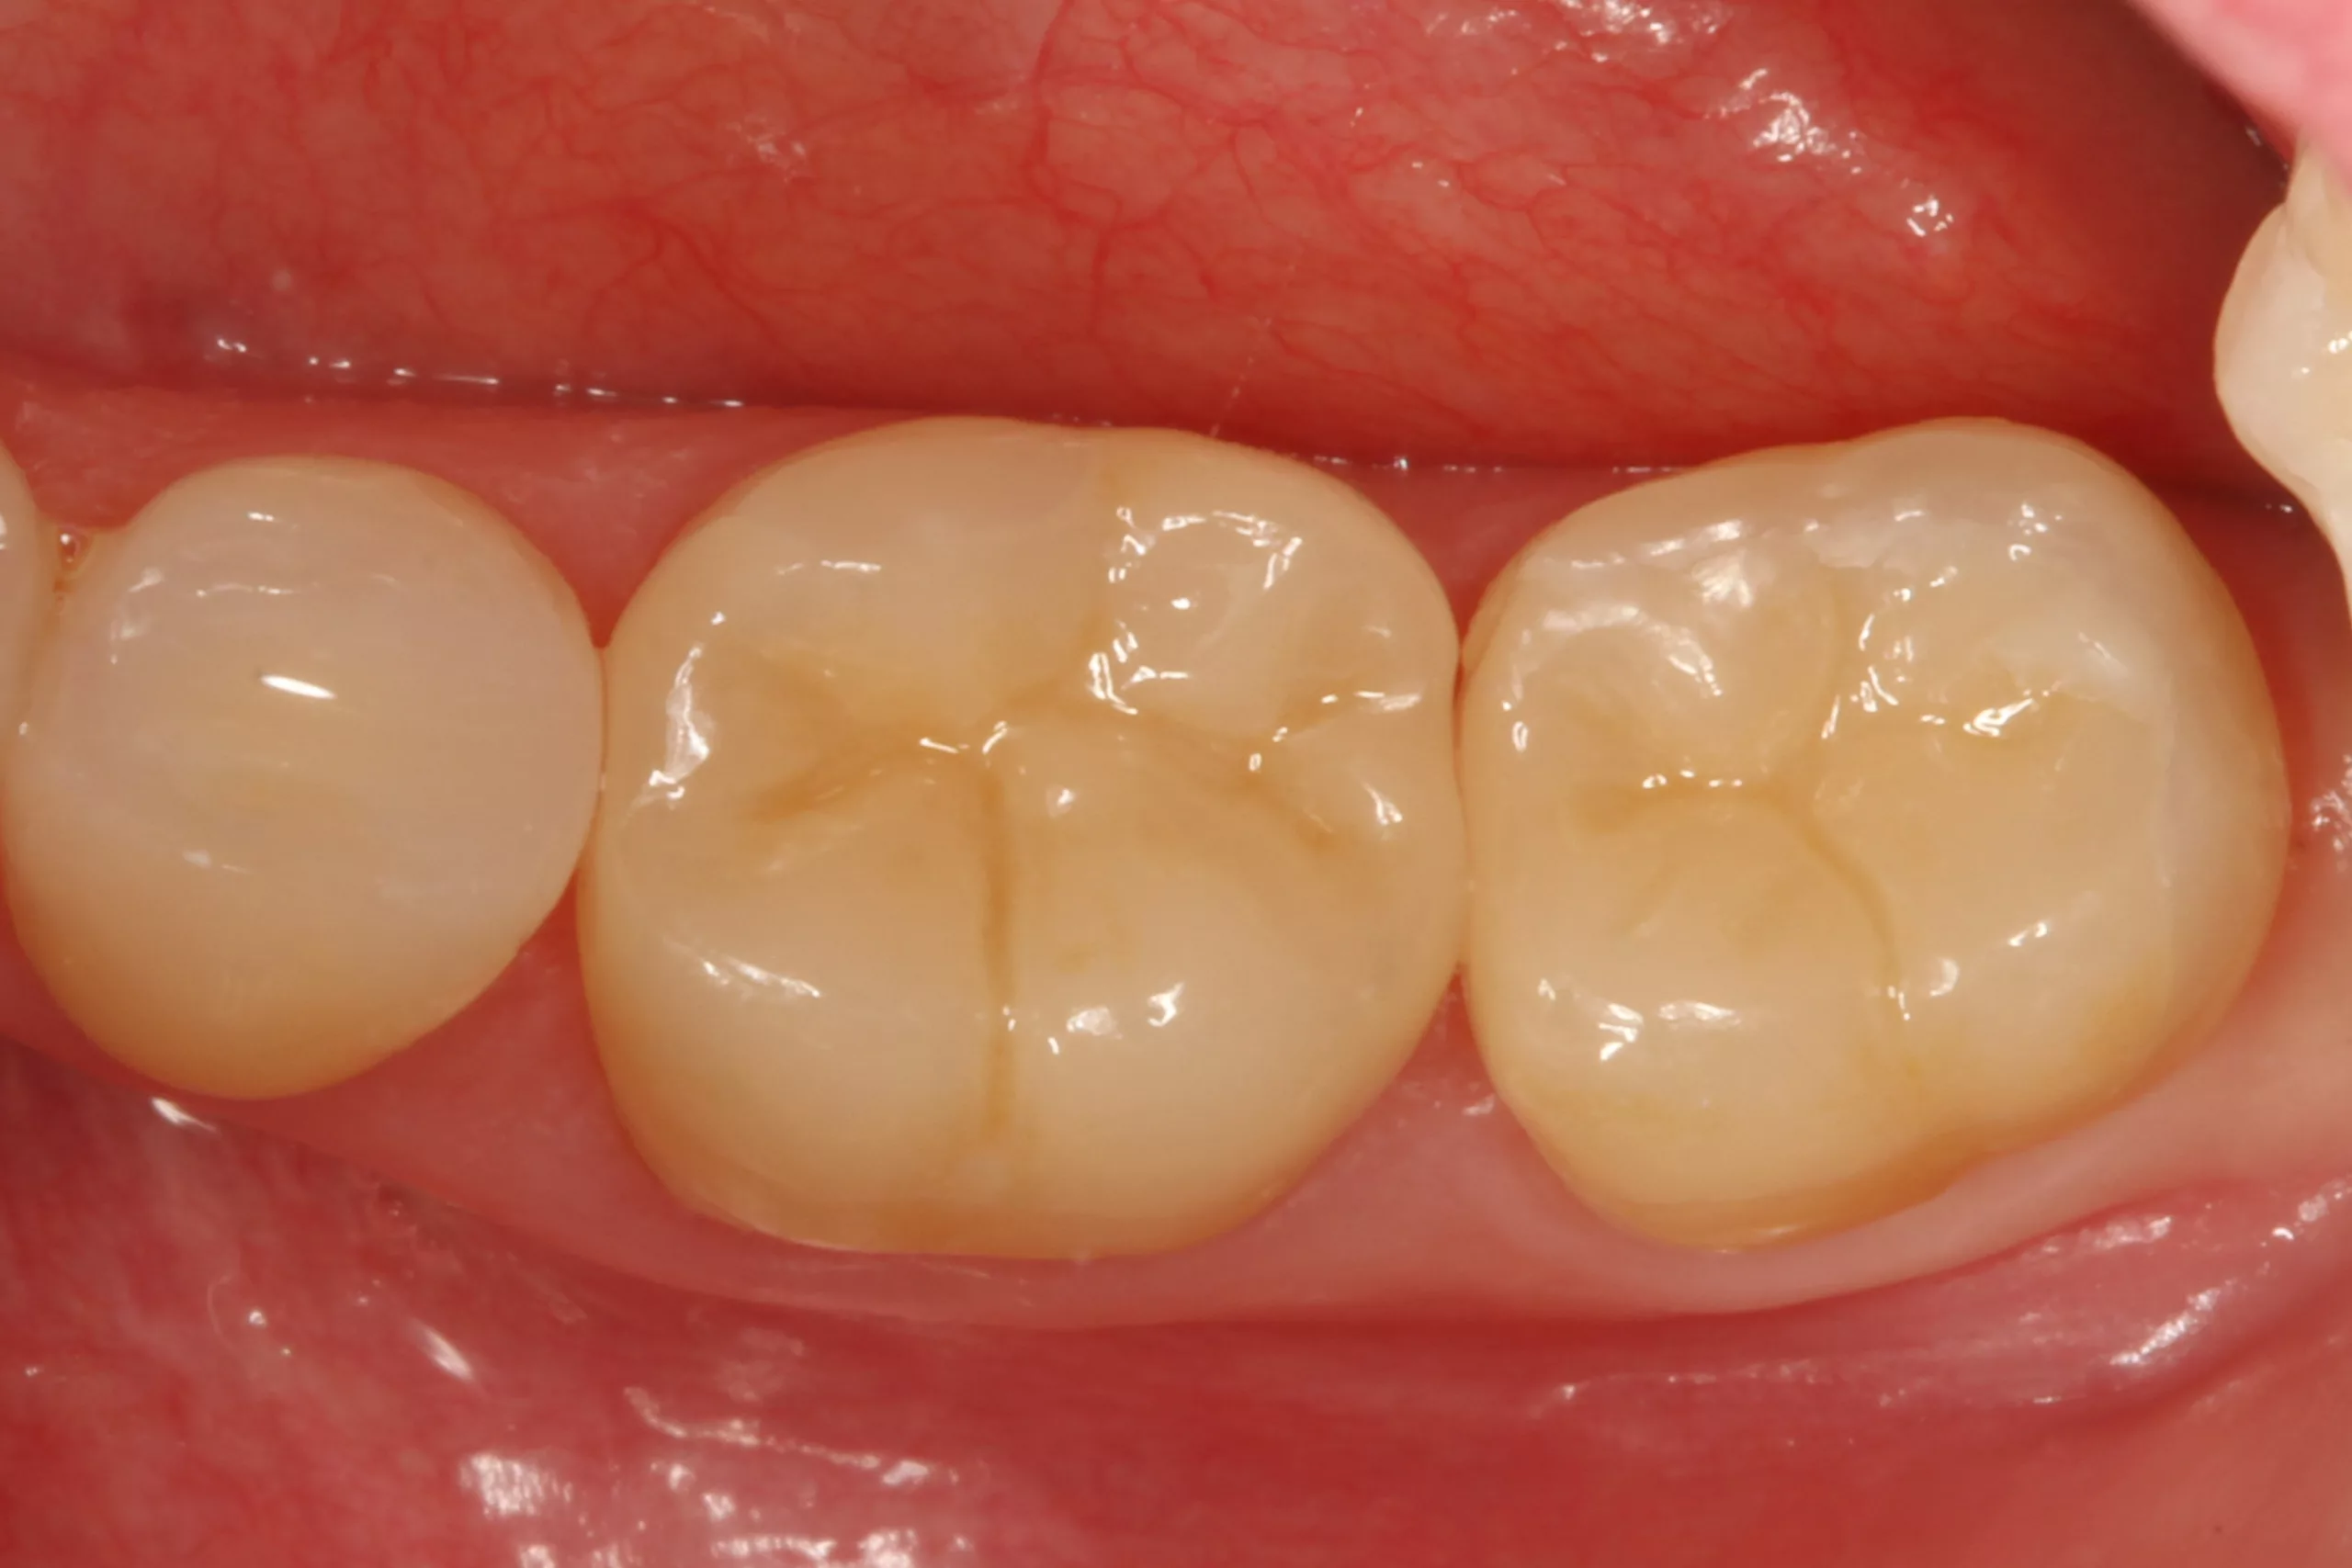

Nach der Schmelzkonditionierung mit dem Phosphorsäuregel und dem ausreichenden Spülen für 15 Sek. ist für eine suffiziente volladhäsive Anbindung ein Benetzungsmittel, ein „Tooth Primer“ erforderlich. Der zu Visalys CemCore gehörende Visalys Tooth Primer ist ein selbstkonditionierender Einkomponenten-Primer, der keiner separaten Lichthärtung bedarf und somit die Ansprüche an die Selbsthärtung des Adhäsivs, die anschließend im Kontakt mit Visalys CemCore abläuft, erfüllt. Die Abbildung 3 zeigt die Einwirkung des Visalys Tooth Primers auf die Präparationsflächen der beiden Zähne 46 und 47. Die Befestigung der Teilkronen erfolgte gleichzeitig mit Visalys CemCore in der Farbe Universal (A2/A3), das vorab direkt auf die Teilkronen und nicht in die Kavitäten appliziert wurde (Abb. 4). Obwohl eine „Tack Cure“-Technik-Option zur Verfügung steht, wurden die Überstände des Befestigungsmaterials mittels Modellierspatel, frischem Bondingpinsel und Zahnseide entfernt. Die im Vergleich zu herkömmlichen Befestigungskompositen etwas höhere Konsistenz und bessere Standfestigkeit (kommt primär der Funktion als Stumpfaufbaukomposit zugute) erleichtert die Überschussentfernung immens, da das Material nicht so schnell unkontrolliert wegfließt. Es erfolgte eine initiale Härtung mittels eines Hochleistungs-LED-Polymerisationsgerätes. Zur Verhinderung der Sauerstoffinhibitionsschicht kann jedes herkömmliche Glyceringel verwendet werden. Alternativ kann die ebenfalls von Kettenbach angebotene Visalys CemCore Try In-Paste zur Anwendung kommen. Obwohl Visalys CemCore eine ausgezeichnete Selbsthärtung aufweist, erfolgte dennoch eine Lichthärtung unter Glyceringel für 20 Sek. pro Fläche. Die Überprüfung der statischen und dynamischen Okklusion darf erst nach Abschluss der Dunkelhärtung vorgenommen werden, damit die adhäsive Integration nicht gestört wird, wenn im Polymerisationsprozess durch Exkursionsbewegungen mechanisch auf die Klebefläche eingewirkt wird.

Die Abbildung 5 zeigt das klinische Endergebnis bei einer Kontrolle nach 2 Monaten: Die beiden Lithiumdisilikat-Teilkronen fügen sich ästhetisch harmonisch in die umgebende Zahnhartsubstanz ein. Das Befestigungskomposit verbindet Zahnhartsubstanz und Restauration perfekt, zeigt keinerlei Verfärbungstendenz und lässt sich farblich weder von der Restauration noch von der Zahnhartsubstanz differenzieren. Klinisch zeigten sich keinerlei postoperative Beschwerden und eine hochzufriedene Patientin.